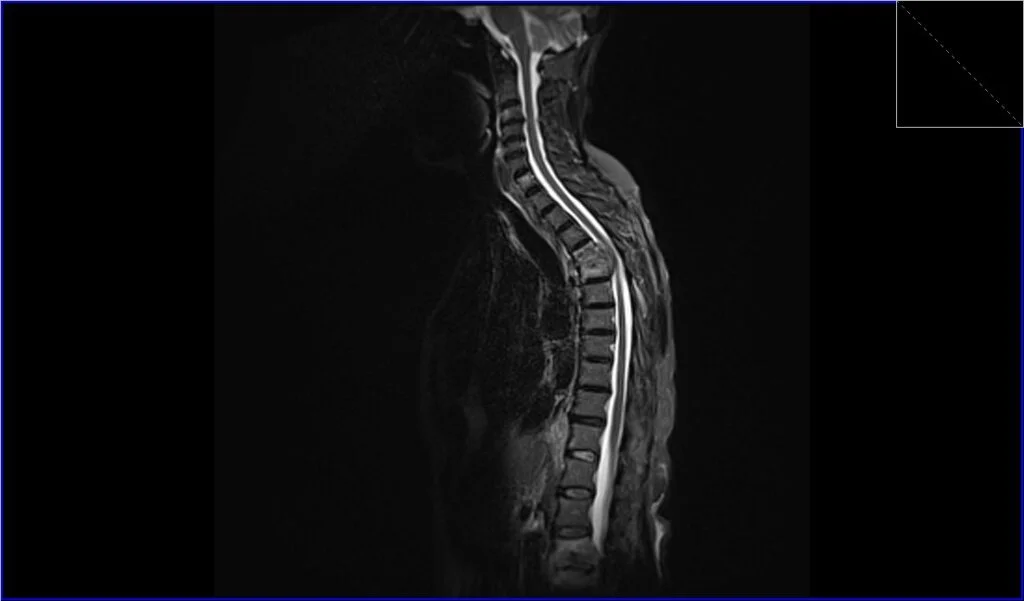

STIR sagittal image shows Metastatic Spinal Cord Compression

T1 TSE sagittal image shows Metastatic Spinal Cord Compression